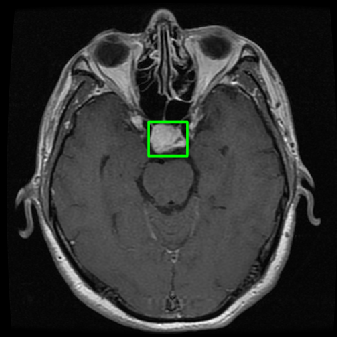

From the above discussions, we have discovered the significant potential of applying Retinex theory to image segmentation and explored its fundamental differences from traditional models. Traditional image segmentation models typically focus on the impact of intensity information on the segmentation results. Therefore, when faced with complex segmentation scenarios, the segmentation results are often affected by lighting, artifacts, and unclear boundaries in the image. As shown in Fig. 1, we present the results of the classical local model LIF [ZHANG20101199] for segmenting brain tumor images along with surrounding tissue edema. The irregular ring-like enhancement caused by the edematous tissue leads to irregular boundaries and low contrast in the images. Consequently, the LIF model can only identify the central necrotic and liquefied regions of the tumor, failing to detect the boundaries and becoming trapped in local minima. In this paper, we draw inspiration from the Retinex theory, which is widely applied in the field of image enhancement. According to Retinex theory, the reflectance component characterizes the intrinsic structural properties of the observed image and preserves texture information independent of illumination variations. By integrating this reflectance component into the level set framework, our model achieves robust segmentation of medical images even under severe intensity inhomogeneity. In addition, a linearized Structural-Prior is proposed to restore intensity consistency and capture local geometric features, thereby improving boundary localization in complex or blurred regions. Furthermore, a relaxed binary level set representation is employed to enhance robustness against noise and to enable accurate tracking of complex contours. Based on these innovations, we propose a novel variational reflectance-based level set model (RefLSM) that simultaneously corrects bias fields and performs segmentation. Experimental results demonstrate that RefLSM significantly outperforms conventional level set methods in both segmentation accuracy and robustness. We present the results of our model segmenting the two brain tumor images mentioned above in Fig. 2.

To address the challenge of segmenting images with severe intensity inhomogeneity, we propose a linearized structural prior that directly operates on the reflectance component . Reflectance-based structural information is more robust to illumination variations and bias field distortions, helping preserve weak edges and subtle anatomical boundaries. As shown in Fig. 2, our method can accurately delineate tumor boundaries and surrounding edema even under severe inhomogeneity, where traditional intensity-based models often fail. The proposed prior aligns smoothed reflectance gradients with data-driven directions, enhancing inter-region contrast, preserving weak edges, and stabilizing the evolution of . Formally, we define the linear structure operator as the gradient field of the smoothed reflectance: